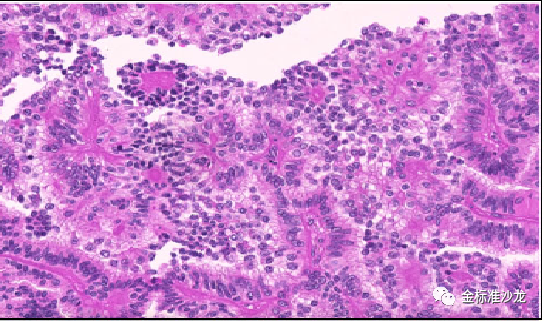

因常存在乳头状或管状乳头状癌区域和高级核特征,包括过去常被错误诊断为2型pRCC的还包括MiTF家族(包括TFE3重排的和TFEB重排的RCC和TFEB扩增RCC,图2,3),新的实体嗜酸性实体和囊性(ESC)-肾细胞癌,管状囊性肾细胞癌和集合管癌。另一个实体粘液管状和梭形细胞癌由于具有不同的染色体改变和Hippo通路肿瘤抑制基因的双等位基因失调,已独立于1型pRCC,尽管二者存在形态及免疫组化重叠。

图2 TFE3重排RCC可见乳头状的结构,高级别核特征,细胞淡染或嗜酸,类似于2型pRCC。免疫组化提示TFE3弥漫强阳性表达